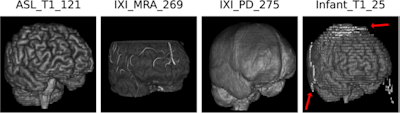

Skull-stripping results of the proposed algorithm. Shown are examples from the Synthstrip test dataset, including T1, magnetic resonance angiography (MRA), proton density (PD) and infant T1 scans. The proposed methods produce sound results, but might struggle with parts of infant brains.Courtesy Rempe, Heine et al, European Radiology

The methods included for the skull-stripping dataset were T1-weighted MR angiography, proton density (PD), and infant brain scans. The authors noted that the algorithm had some difficulty in skull-stripping infant brain scans, leaving some residue in the output.